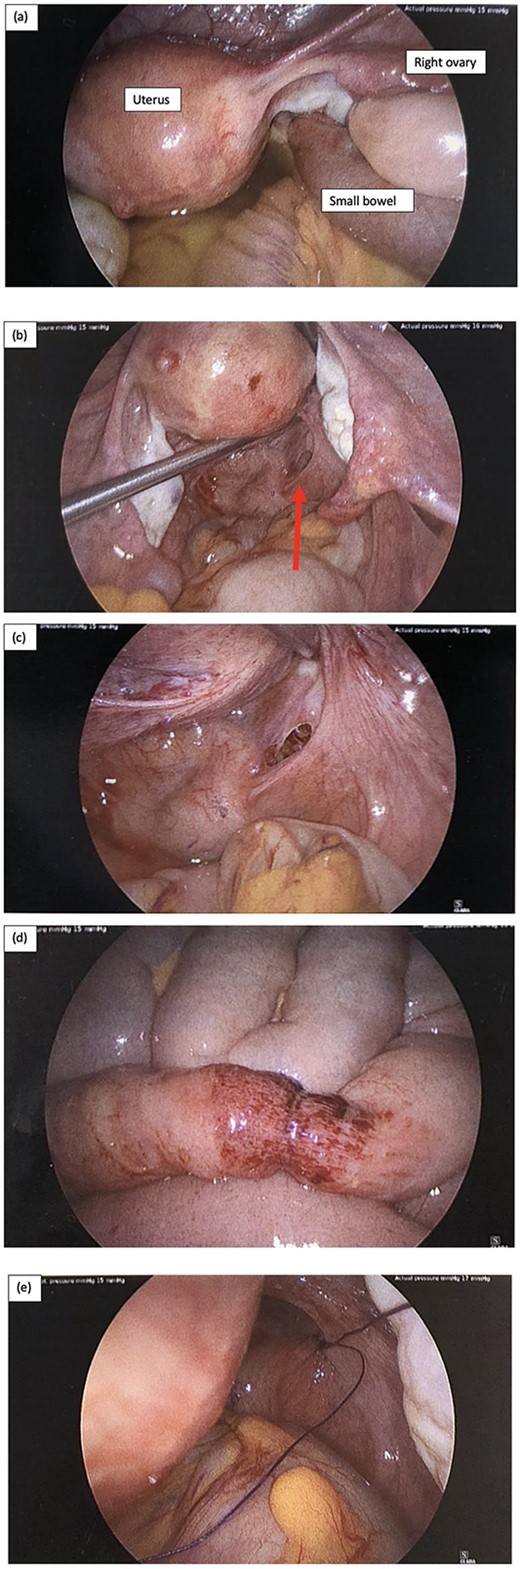

Patient was operated on within 2.5 hours of surgical assessment. Laparoscopic surgery was performed with 12-mm Hassen optical infraumbilical port and 3 further 5 mm ports in the suprapubic, left iliac fossa and right iliac fossa regions. Intraoperative findings are demonstrated in Fig. 2.

Intraoperative laparoscopy findings, and (a) key landmarks including the uterus and right ovary are identified, as well as a short segment of small bowel diving deep into the pelvis, and there is also moderate volume of serous free fluid; (b) serous fluid has been suctioned and there is small bowel herniating through a small peritoneal defect adjacent to the rectum on the right represented by the red arrow; (c) peritoneal defect in the POD; (d) the short segment of small bowel that was involved incarcerated in the hernia has a small area of bruising but is otherwise viable, and (e) the peritoneal defect was repaired with a single figure of 8 stich using 0 PDS suture.

There was a finding of a nubbin of small bowel herniating through a small peritoneal defect at the peritoneal reflection adjacent to the rectum on the right and moderate serous free fluid was identified (Fig. 2a–c). The small bowel was reduced easily with gentle traction using laparoscopy instruments and a single figure of 8 repair using 0 PDS suture was used to close the peritoneal defect (Fig. 2e). The short segment of small bowel which was incarcerated within the hernia was bruised as shown in Fig. 2d but viable. The small bowel was examined from duodenum to the terminal ileum and no other injuries were identified. The appendix was also mildly injected and removed laparoscopically. Patient was allowed sips of clear fluid postoperatively and NGT continued on free drainage and 4-hourly manual aspirations.